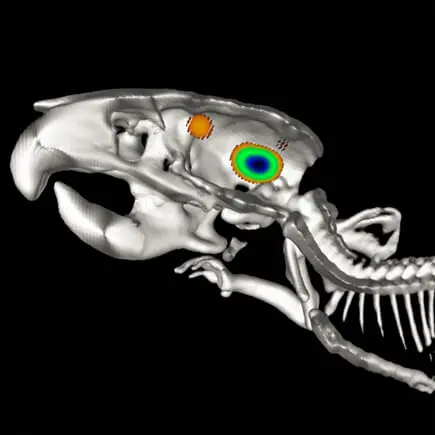

Metastaza nowotworu, znakowanie bioluminescencyjne: IVIS Spectrum CT